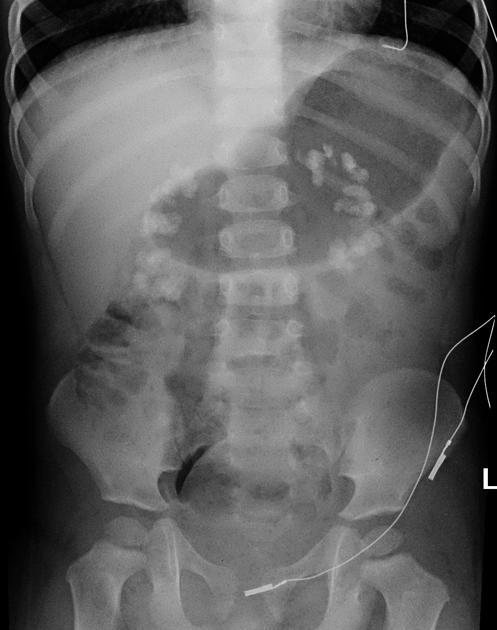

Diagnosis?

Medullary nephrocalcinosis.

95% of cases are due to primary hyperparathyroidism, distal renal tubular acidosis (type 1), or medullary sponge kidneys.

But it can be caused by anything that causes hypercalcemia, hypercalciuria, or hyperoxaluria (others include milk alkalai syndrome, multiple myeloma, hypervitaminosis D, Cushing syndrome).